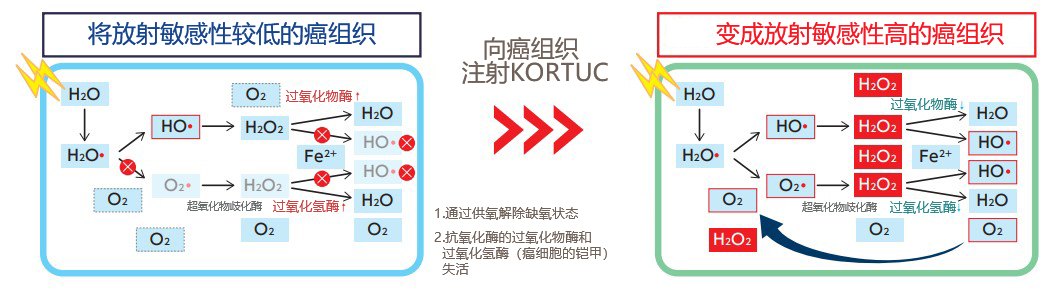

(圖1)缺氧狀態下的癌細胞即使照射放射線,也不會生成或者維持攻擊癌細胞的高反應性自由基,因此治療效果有限(左)。但向癌細胞注射KORTUC后,可以使抗氧化酶失活并供氧,能維持照射放射線生成的自由基。此外,過量的過氧化氫會在溶酶體中產生自由基,誘導細胞凋亡,從而增加細胞殺傷效果。

X射線的弱點是對直徑大于1厘米,缺氧條件下的實體瘤無效。而KORTUC的機制之一是使這些腫瘤重新氧化。